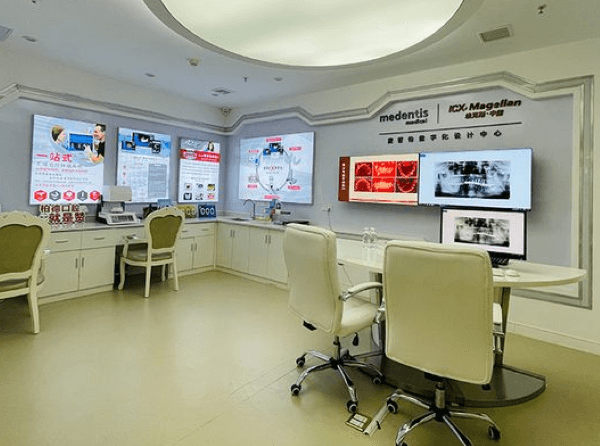

广州柏德口腔医院是经过相关部门审核通过的正规口腔医疗机构,院内设有德系数字化种植中心、德系数字化正畸中心、德系数字化美牙修复中心、德系综合治疗中心等等,致力于为广大群众提供优质的口腔诊疗服务,而且他们家还是医疗保险的定点机构,部分口腔还可以使用社会医疗保险卡进行支付。

广州柏德口腔采用数字化诊疗模式为患者进行牙齿治疗,像种植牙方面就是利用3D打印机将种牙数据信息做成3D数字化导板,采用微创的形式进行手术,这样能够减少种牙的时间,能够避免种牙的误差,还能够避开神经、血管等关键的组织,减轻种植牙带给患者的疼痛感,还能够根据患者的不同情况,制定个性化治疗方案,更好的解决患者牙齿问题,整体舒适度是非常高的。